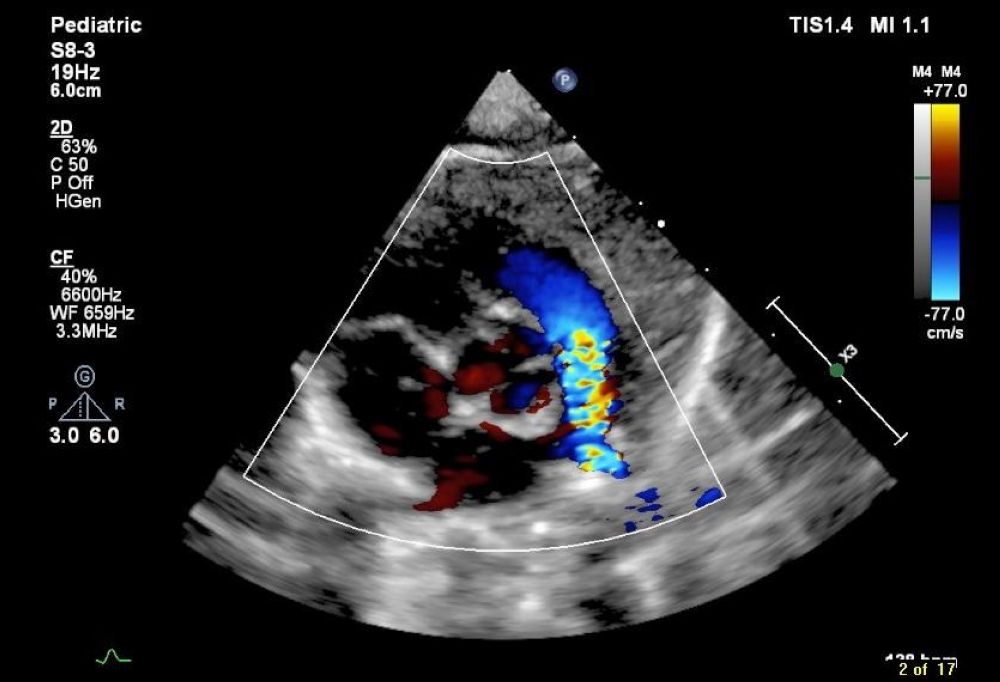

وأوضح تجمع القصيم الصحي أنه بعد إجراء الفحوصات الطبية اللازمة، التي شملت الكشف السريري، وأشعة صدى القلب، وتخطيط القلب، والتحاليل المخبرية والإكليلية، أظهرت النتائج وجود ضيق حاد في الصمام الرئوي وانحسار شديد في تدفق الدم.

أشار التجمع إلى عرض الحالة على فريق مختص في قسطرة قلب الأطفال بالتعاون مع أطباء التخدير، وقرر الفريق إجراء عملية قسطرة قلبية لتوسيع الصمام الرئوي.